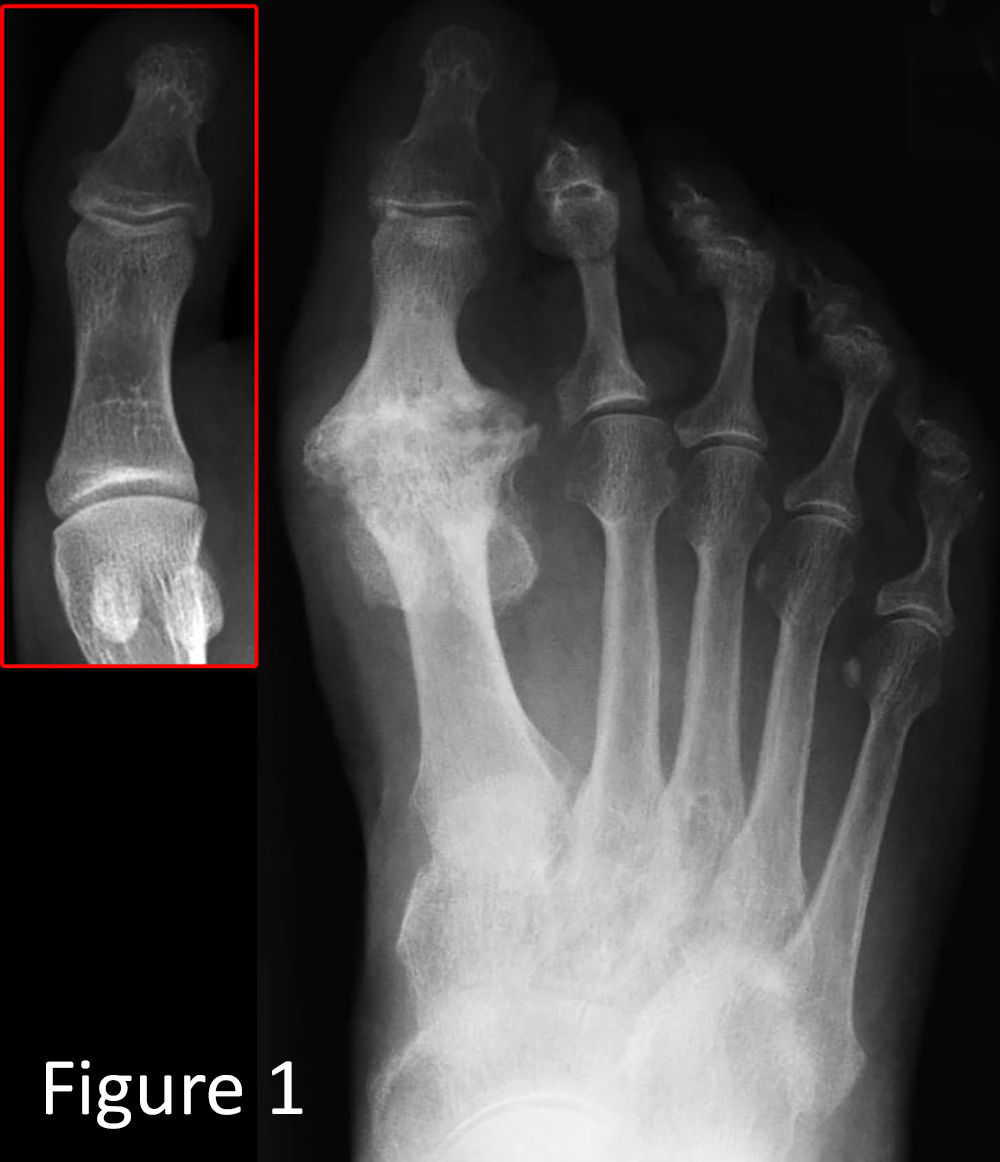

As seen on the X-ray in Figure 1, arthritis of the big toe joint is present, with significant bone spurs around the joint.

There is no cartilage, the joint space has disappeared, and bone spurring is marked around the joint. You can see that the big toe joint on the right has a large bump. This is not a bunion but arthritis (hallux rigidus).